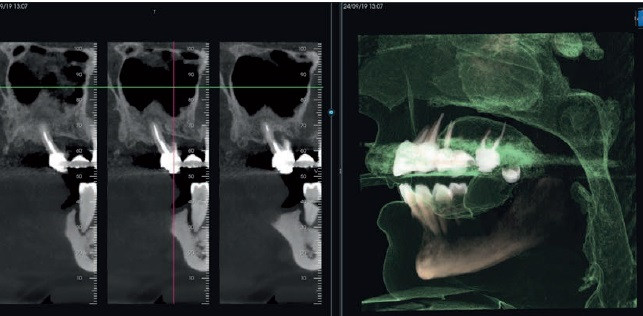

NeoWise beeldvormingssoftware is ontworpen rond de gebruiker en de patiënten. Hiermee kan men

2D- en 3D-beelden beheren/verwerken, zodat nauwkeurige diagnoses worden gesteld en communicatie met de patiënt gestroomlijnd. Eenvoudig en effectief, met geavanceerde diagnose/planning hulpmiddelen en filters.

NeoWise integreert geautomatiseerde AI-gestuurde functies die diagnoses verbeteren, de

de operationele efficiëntie verhogen en de behandeling meer personalieren voor elke patiënt, waardoor het werk preciezer en gerichter wordt dan ooit.